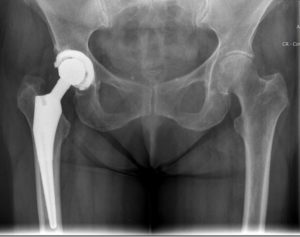

Il paziente quando presenta queste problematiche può rivolgersi allo specialista per una valutazione obiettiva, il quale riscontrerà una limitazione dell’anca nei movimenti di flessione ed intra e extra rotazione caratterizzati da dolore inguinale aggravato anche dalla mobilizzazione passiva ai massimi gradi. Una volta accertate queste caratteristiche si dovrà svolgere un esame strumentale, la radiografia con la quale si accerterà l’entità della problematica.

Una volta che lo specialista ha fatto una diagnosi della patologia, andrà a valutare la possibilità di svolgere un percorso conservativo, attraverso una riabilitazione guidata, oppure nel caso di una situazione cronica si dovrà ricorrere alla chirurgia, attraverso la sostituzione dell’articolazione con una protesi d’anca.